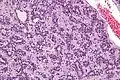

Micrograph of an adenomyoepithelioma. H&E stain. | |

An adenomyoepithelioma of the breast is a rare tumour in the breast composed of glandular elements (adeno-) and myoepithelial cells. It is usually benign;[1] however, there are reports of malignant behaviour.[2]

The histomorphologic appearance can mimic invasive ductal carcinoma, the most common type of invasive breast cancer.